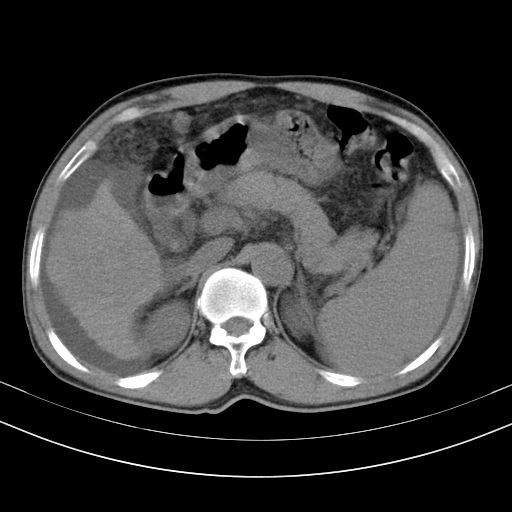

以下是引用随光逐影在2010-2-28 10:23:00的发言:[br]1)考虑肝癌;建议行ct增强扫描检查。2)肝硬化,脾大,腹水。3)慢性胆囊炎。

以下是引用dyqct在2010-2-28 16:44:00的发言:[br][quote]以下是引用随光逐影在2010-2-28 10:23:00的发言:[br]1)考虑肝癌;建议行ct增强扫描检查。2)肝硬化,脾大,腹水。3)慢性胆囊炎。